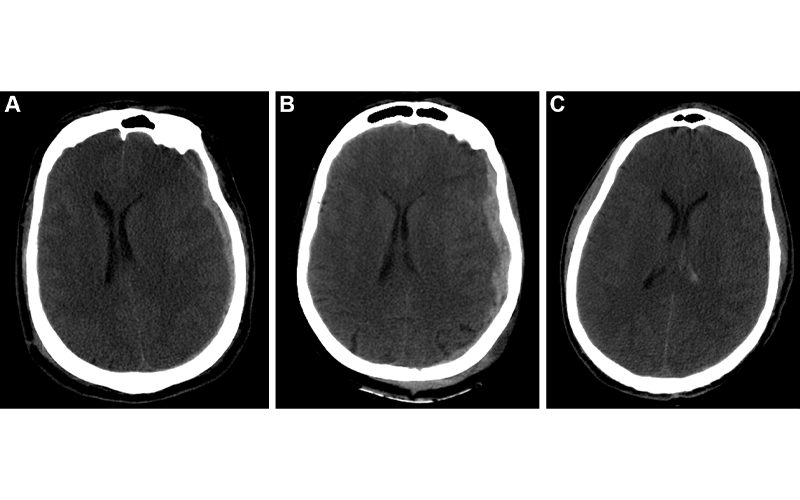

Example predictions by fusion model on University of Pittsburgh Medical Center patients. (A) Correct prediction in a 44-year-old man who was involved in an unrestrained motor vehicle collision. He underwent emergent decompressive hemicraniectomy (DHC), had bilateral lung injuries, and ultimately developed a pulmonary embolism with difficulty oxygenating on posttrauma day 6. His care was withdrawn, and he died. The model correctly predicted mortality. (B) Incorrect prediction in a 57-year-old woman who was in a motor vehicle collision and underwent DHC. The model predicted she would die, but she had a Glasgow Outcomes Scale of 3 at 2 years after trauma. She lived in a nursing home and was dependent on others for most daily living activities. (C) Incorrect prediction in a 28-year-old man who was in a motorcycle collision and had a minor head injury with intraventricular hemorrhage. Several weeks after trauma, he developed Klebsiella ventriculitis and pneumonia that led to an episode of severe hypotension. He subsequently developed malignant cerebral edema and died by brain death criteria. While the model predicted this patient would survive, this scenario highlights the difficulty of predicting outcomes based on information available in the emergency department, as events later in the patient’s course affect outcomes. https://doi.org/10.1148/radiol.212181 ©RSNA 2022